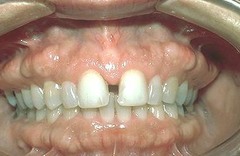

Hutchinson Incisors (see image)

appear notched caused by syphilis

Hutchinson's incisors